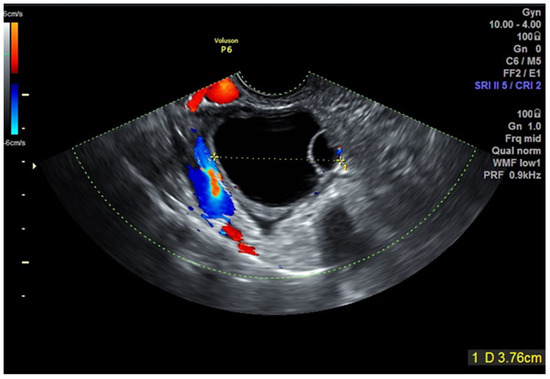

| 5 | 36 | 0 | Right | 47 | Unilocular cystic low-level echogenicity | Yes | Rectovaginal nodule | Endometrioid lesion (complex hyperplasia without atypia) | 34 | Normal follow-up. Infertility-repeated IVF cycles, no pregnancy. |